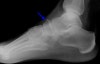

X-ray에서 발견하지 쉽지 않아 종종 놓치기도 합니다.

Oblique 45' view는 tuberosity fractures를 발견하기 유용합니다.

X-ray : 주상골 골절(Dorsal avulsion fracture)